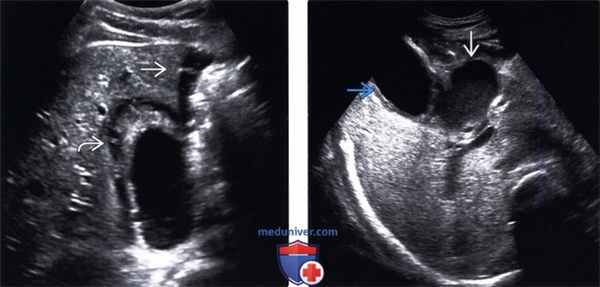

(Левый) Положение пациента лежа на спине. На поперечном УЗ срезе визуализируются утолщенная отечная стенка желчного пузыря и смещающийся книзу под действием гравитации сладж (конкременты не видны). Обратите внимание на неоднородное скопление жидкости с медиальной стороны от печени.

(Правый) Случай перфоративного острого холецистита. Поперечный УЗ срез. С медиальной стороны от желчного пузыря с утолщенными стенками определяется скопление низкоэхогенных сигналов (абсцесс).